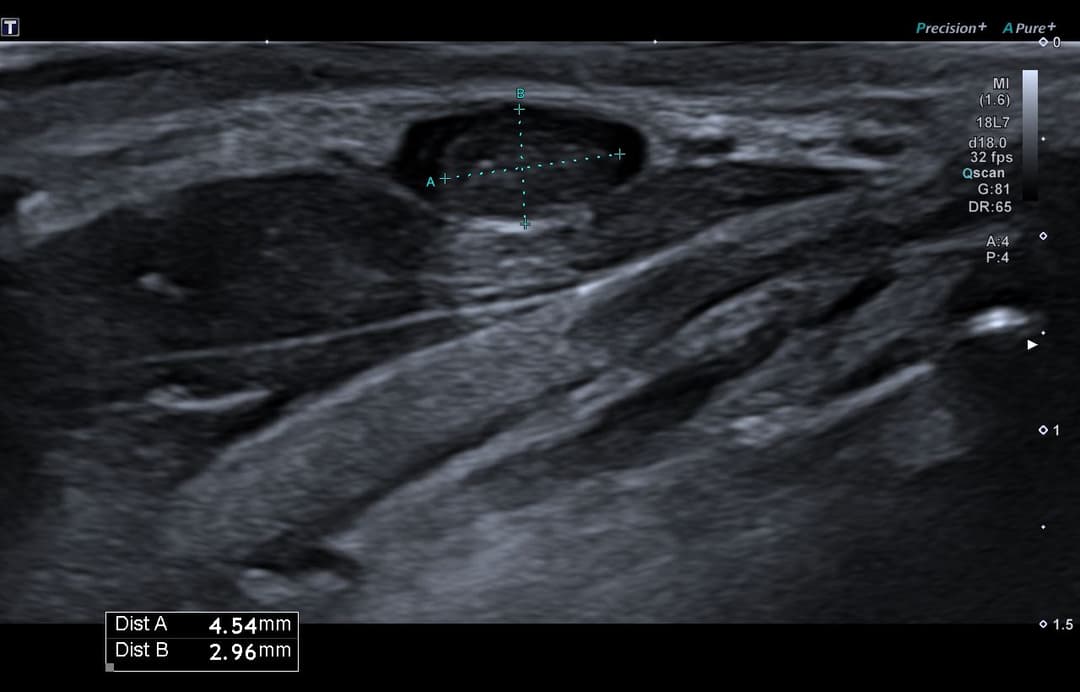

Échographie

Matériel échogène tissulaire endoluminal dans une veine superficielle collatérale de la veine jugulaire externe droite, présentant un pédicule vasculaire en Doppler couleur.